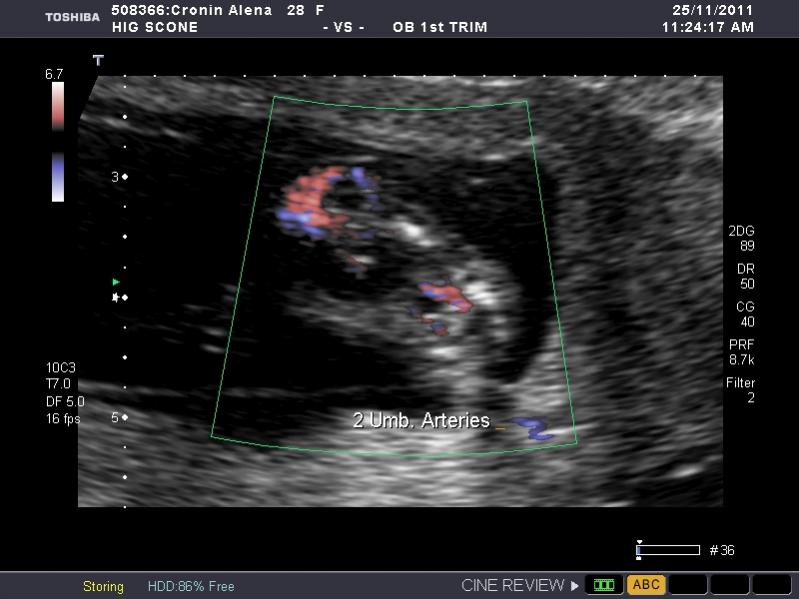

I have heaps of photos and I don't know what I am looking at so if the photo I post isn't showing anything let me know and I will try another. I am nervous as anything because I so so want a girl, but of course would still be happy with a boy. The ultrasound tech wouldn't guess.

So what is your guess.